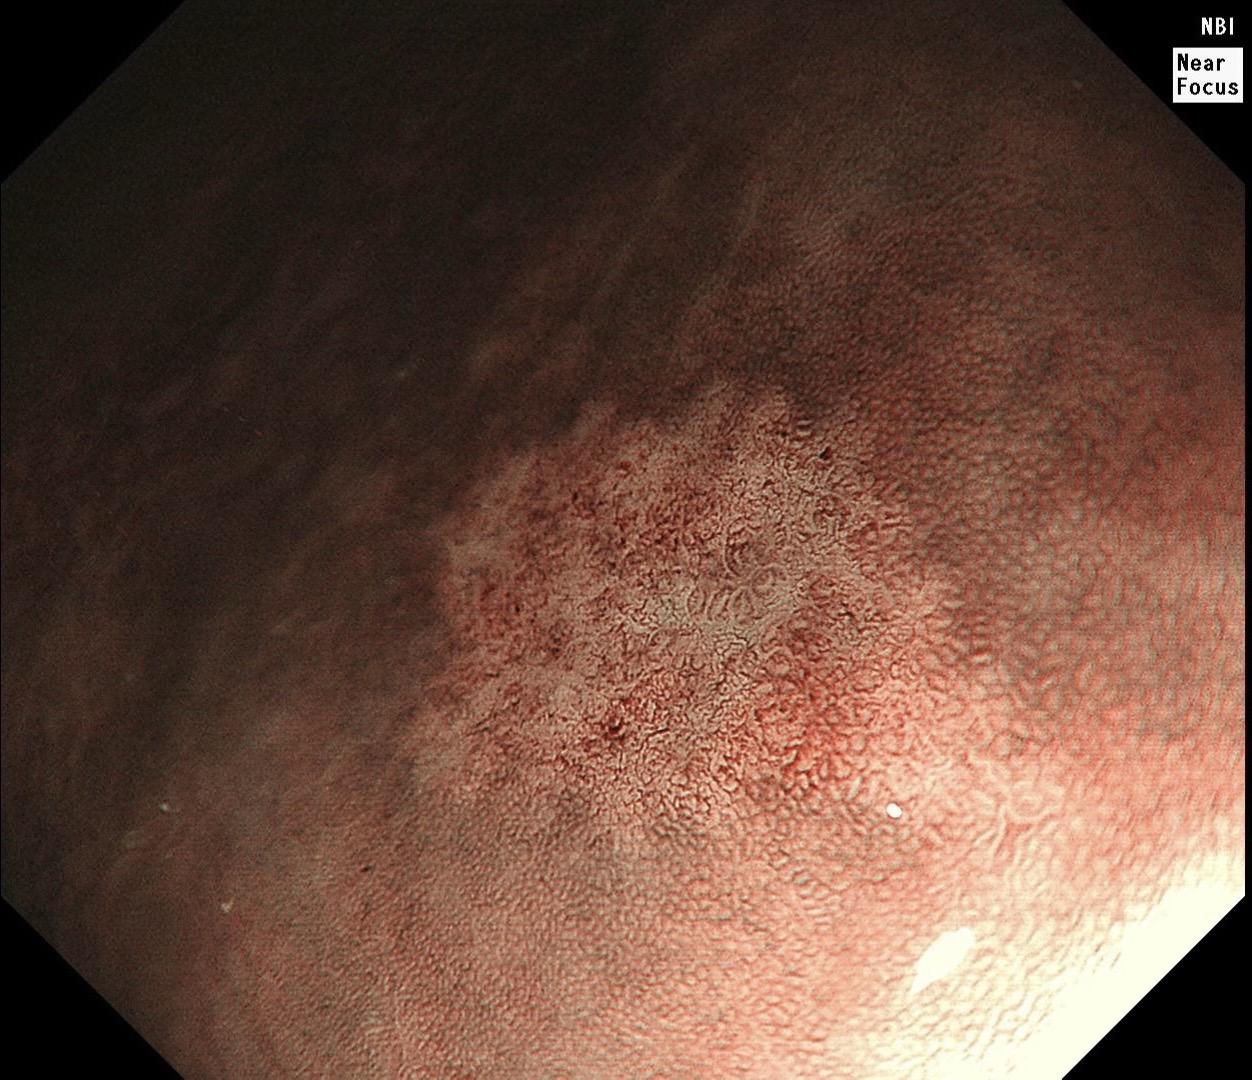

男,40岁,胃双发褪色调病变。慢性胃炎复查,3年前胃镜未见异常,Hp阳性背景,萎缩不明显,胃体下部大弯见一褪色调病变,浅凹陷,5mm左右,换用放大内镜观察,表面结构缺失,血管异型明显,未分化可能性大……胃窦后壁见一白斑,无高度差,NBI浅茶色,放大草草看了下,似有边界,IP增宽,活检待病理……小哥哥胖得几乎没脖子,腹式呼吸太明显~😖